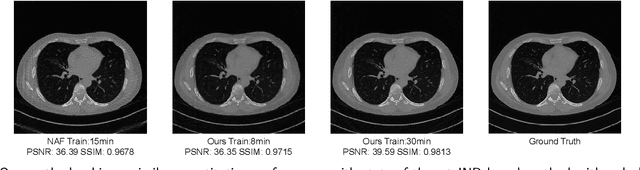

Sparse-view CT is a promising strategy for reducing the radiation dose of traditional CT scans, but reconstructing high-quality images from incomplete and noisy data is challenging. Recently, 3D Gaussian has been applied to model complex natural scenes, demonstrating fast convergence and better rendering of novel views compared to implicit neural representations (INRs). Taking inspiration from the successful application of 3D Gaussians in natural scene modeling and novel view synthesis, we investigate their potential for sparse-view CT reconstruction. We leverage prior information from the filtered-backprojection reconstructed image to initialize the Gaussians; and update their parameters via comparing difference in the projection space. Performance is further enhanced by adaptive density control. Compared to INRs, 3D Gaussians benefit more from prior information to explicitly bypass learning in void spaces and allocate the capacity efficiently, accelerating convergence. 3D Gaussians also efficiently learn high-frequency details. Trained in a self-supervised manner, 3D Gaussians avoid the need for large-scale paired data. Our experiments on the AAPM-Mayo dataset demonstrate that 3D Gaussians can provide superior performance compared to INR-based methods. This work is in progress, and the code will be publicly available.